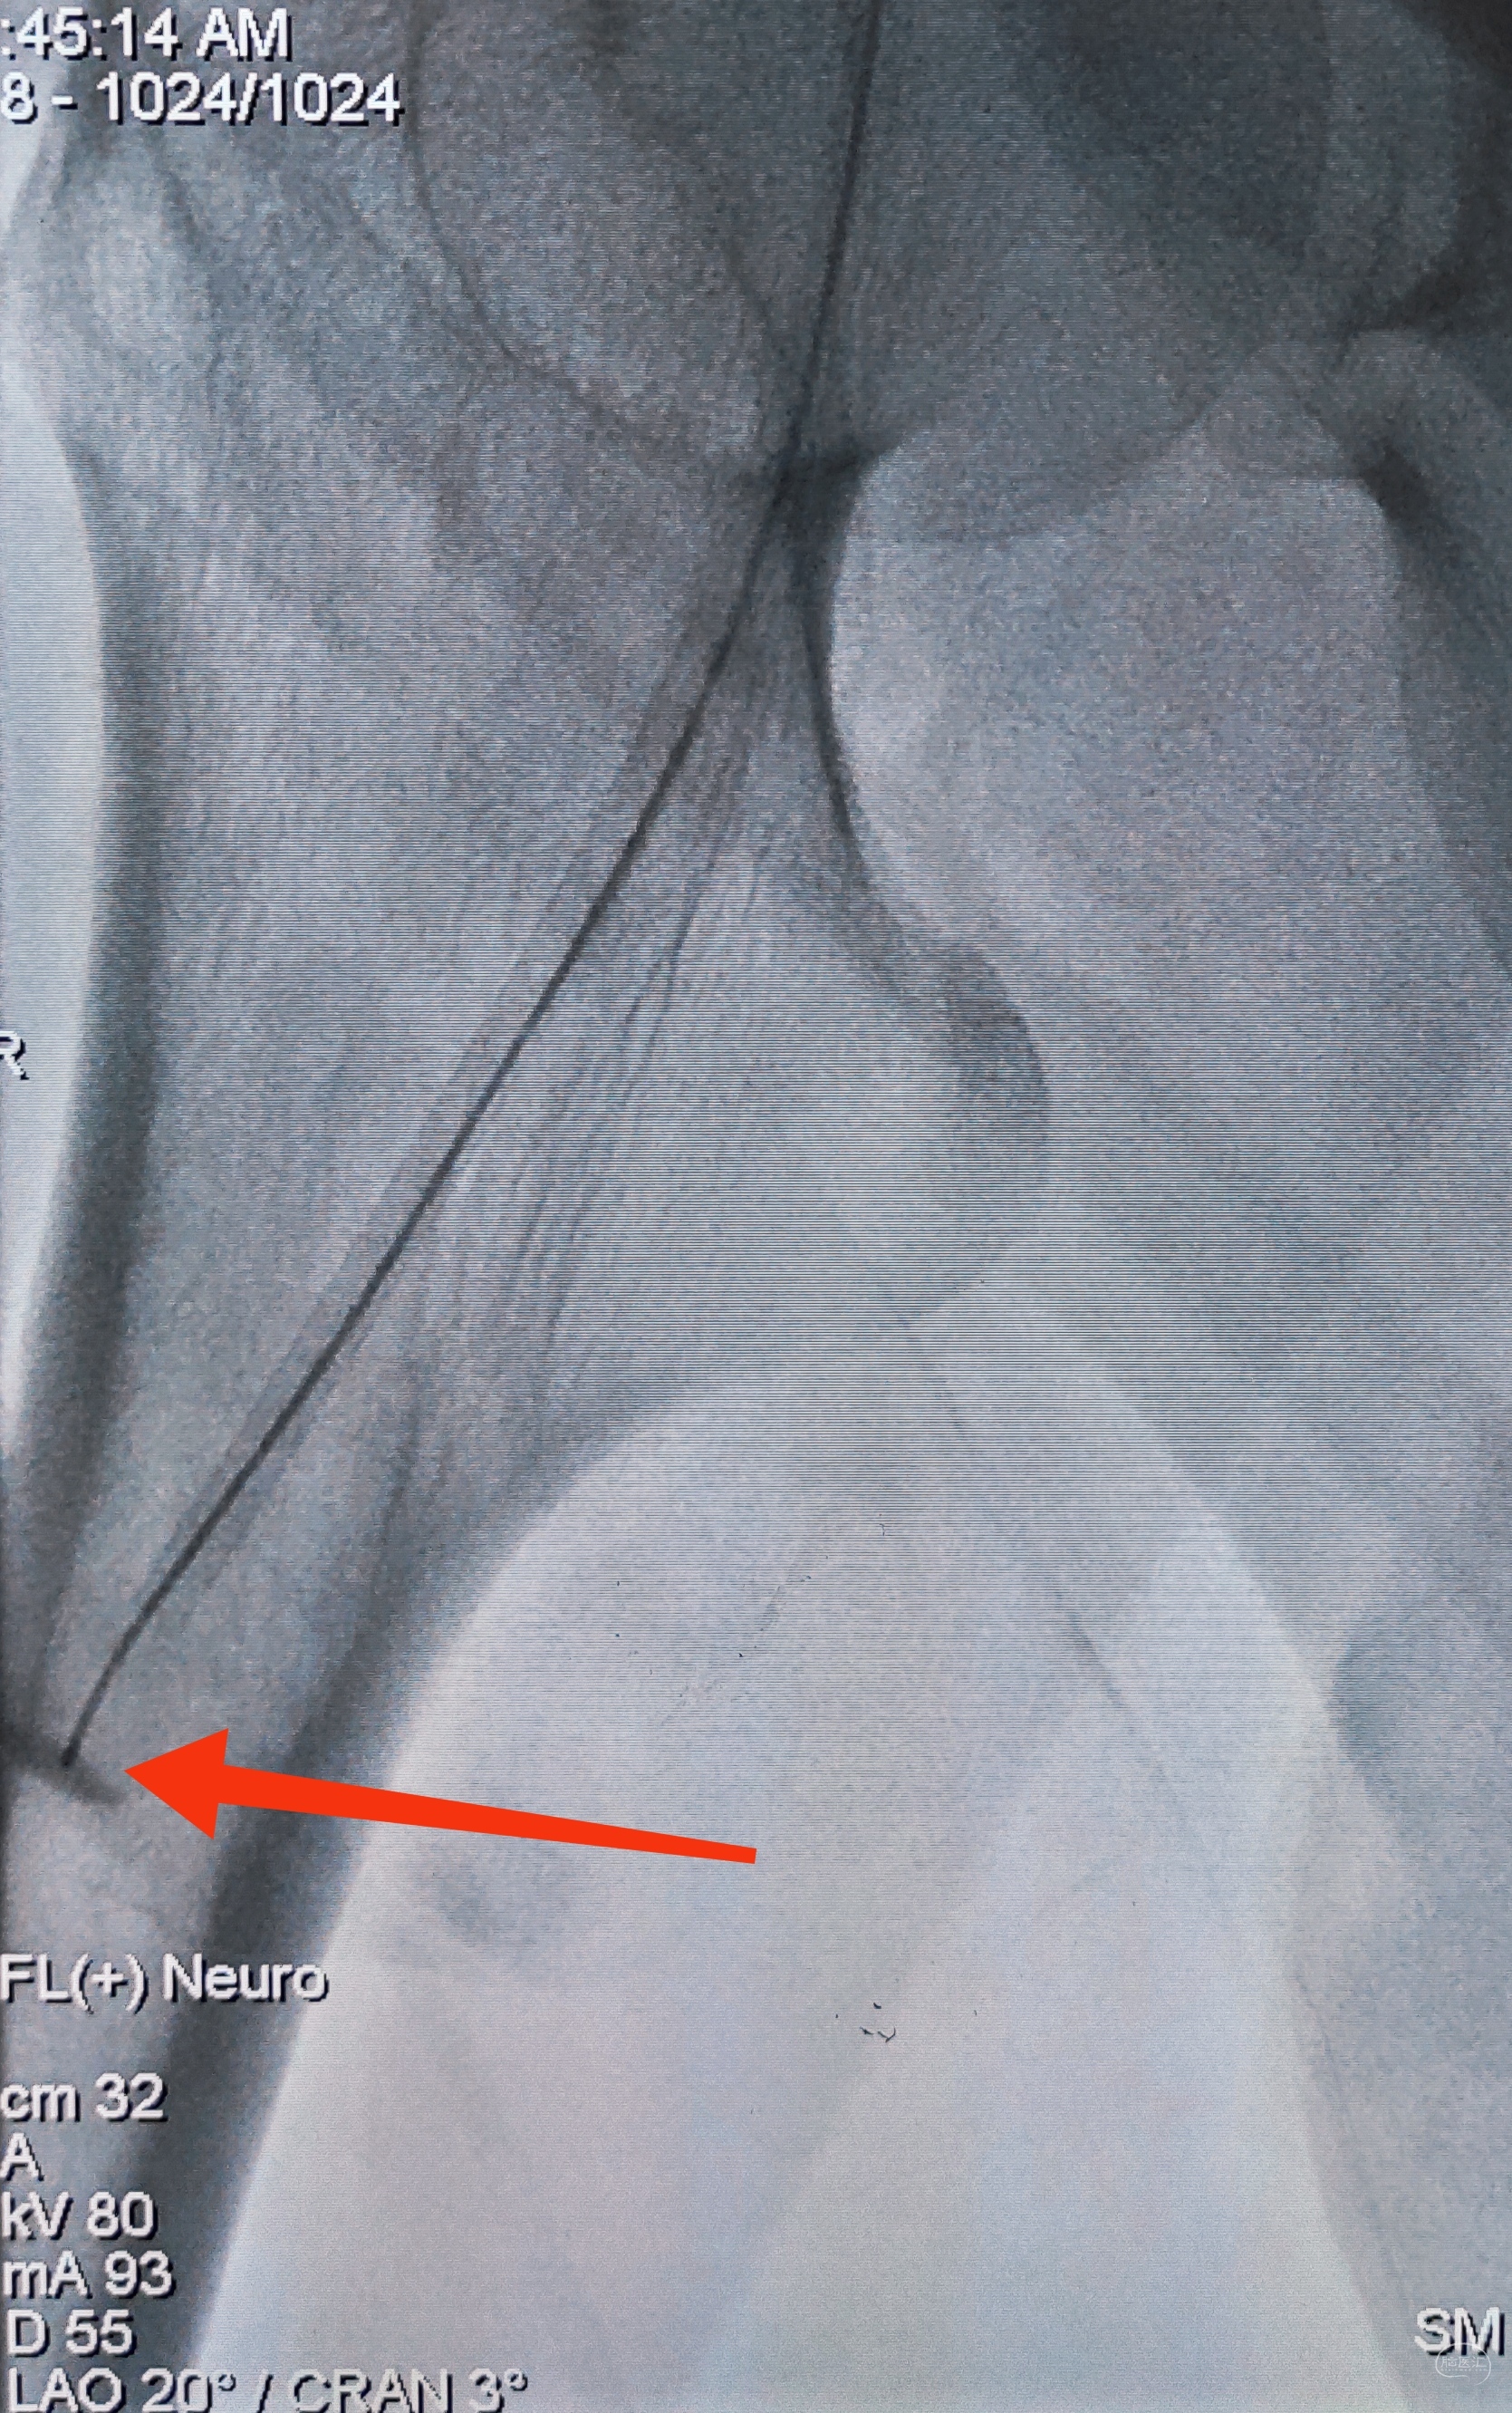

一切看似理想,一切看似简单,诡异的事情还是发生了,8F导引导管死活无法进入左侧锁骨下动脉,各种方法尝试个遍:泥鳅走远,单弯挂口,Sim挂口,屡战屡败(水平退步明显,不应该啊,夹层?),因为怕折腾,因为想安全,怕进假腔,弄出夹层。索性换一个思路:空中接力,构建桡-股动脉大环线

自下向上走不通,那就从上边来

经左侧桡动脉6F导引导管,出加长泥鳅,一路向下,逼近右侧股动脉鞘

以为很难,其实不然,泥鳅头段顺利进入股动脉鞘内,但是问题来了,因为是动脉鞘,有活瓣封口,泥鳅无法逆向穿过动脉鞘入口,何解?

那就利用换鞘技术,桡动脉侧持续给泥鳅张力并顶住(助手),缓慢回撤股动脉鞘至体外(主刀),看到泥鳅后抓紧,后拽;长度足够后,带套管重新置入8F股动脉鞘,完成桡-股动脉大环线建立。

泥鳅两段露头,8F导引导管沿泥鳅攀爬,一把干到左侧肱动脉为止

6F导引导管造影确认支架置入部位